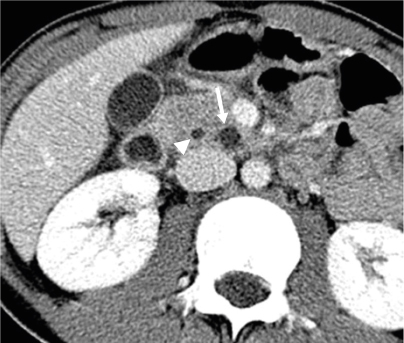

The initial preoperative laboratory data revealed an elevated amylase of 153 U/L and a lipase level of 71 U/L. The liver function tests were otherwise normal except for an elevated alkaline phosphatase of 429 IU/L. Abdominal ultrasonography was performed, which showed a lobulated cystic mass in the pancreas (Fig. 1), and subsequent computerized tomography (CT) showed a mildly inflamed pancreas with a 1.2×0.9×1.3 cm-sized low-attenuating cystic lesion with a pleomorphic appearance at the pancreatic uncinate process (Fig. 2). A magnetic resonance imaging (MRI) scan performed later for cystic evaluation showed pancreatic ductal communication with the cystic lesion along with downstream ductal dilatation. Furthermore, mild dilatation of the main pancreatic duct was observed (Fig. 3). The cystic lesion revealed communication with the dorsal duct and congenital anomaly of the pancreatic duct, and pancreas divisum was suspected due to a lack of fusion of the ventral and dorsal ducts and the common bile duct, which joins with the dorsal duct. Therefore, given the suspicion of IPMN and symptoms of pancreatitis, the patient underwent a pylorus-preserving pancreaticoduodenectomy. The histopathology report revealed BD-IPMN with intermediate-grade dysplasia. The depth was limited to the pancreas without invasion of the surrounding adjacent organs. Pancreatic intraepithelial neoplasia was not applicable, and the mucinous glands were of the intestinal type (Fig. 4).

Fig. 2

Abdominal computerized tomography reveals a small cystic mass (arrow) in the pancreatic uncinate process. The adjacent pancreatic duct (arrowhead) is mildly dilated.